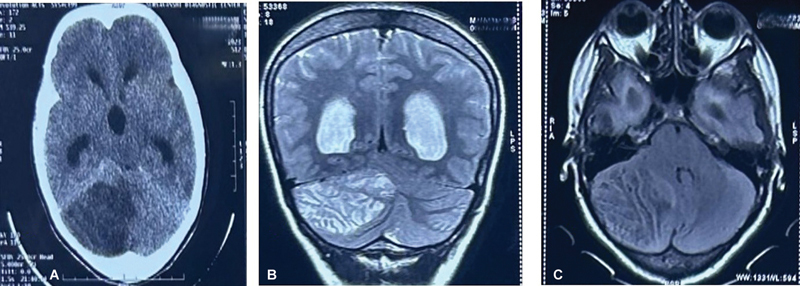

Lhermitte-Duclos disease (LDD) is a rare, autosomal dominant, dysplastic gangliocytoma of the cerebellum. It is a slow-growing benign tumor. The challenges in the surgical resection of these tumors lie in accurately delineating the tumor margin from the normal cerebellar parenchyma. Intraoperative ultrasound has the potential to overcome these limitations. A 30-year-old woman was diagnosed as having LDD showing a typical "tigroid" appearance on MRI. Intraoperative ultrasound was used to delineate the tumor margins and near-total resection was done via right suboccipital craniectomy. The diagnosis was confirmed on histopathological examination. Postoperatively there were no neurological deficits, and the patient is on regular follow-up for screening of Cowden's syndrome. We report this case to highlight the undervalued utility of intraoperative ultrasonography while dealing with patients with LDD. This modality serves as an effective tool to maximize the extent of resection without adding to postoperative morbidity.